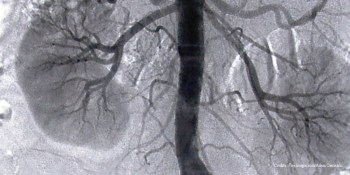

Simple public health intervention can preserve kidney health - Aga Khan University studyKarachi, May 20, 2016: Up to one in five adults in Pakistan have chronic kidney disease, which has become one of the rapidly escalating causes of death. Patients with advanced CKD require dialysis or transplantation, unaffordable for the vast majority of people.

A research paper published in the Clinical Journal of the American Society of Nephrology reveals that simple and inexpensive public health interventions can help prevent many cases of CKD.